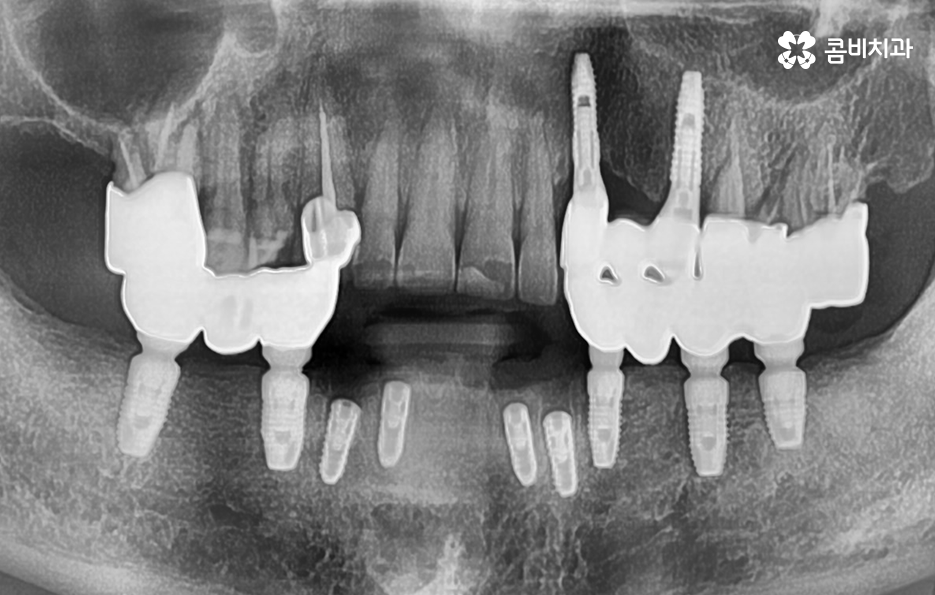

위 사진에서 보시는 것처럼 이미 치주염으로 인해 뿌리가 흔들리는 치아는 한꺼번에 여러 치아를 잃게 되었으며 기존의 임플란트 역시도 약해진 잇몸 뼈와 치료 비용 등을 감안하여 브릿지의 형태로 임플란트가 식립되어 있는 것을 확인할 수 있어요

실제 60대 이후 환자 분들의 경우 치주염으로 인해 잇몸 뼈가 녹아서 치아의 윗니, 아랫니 모두를 잃고 임플란트를 알아보시는 경우도 많으며 빠르면 50대에도 이러한 케이스의 환자분들을 볼 수 있는데요